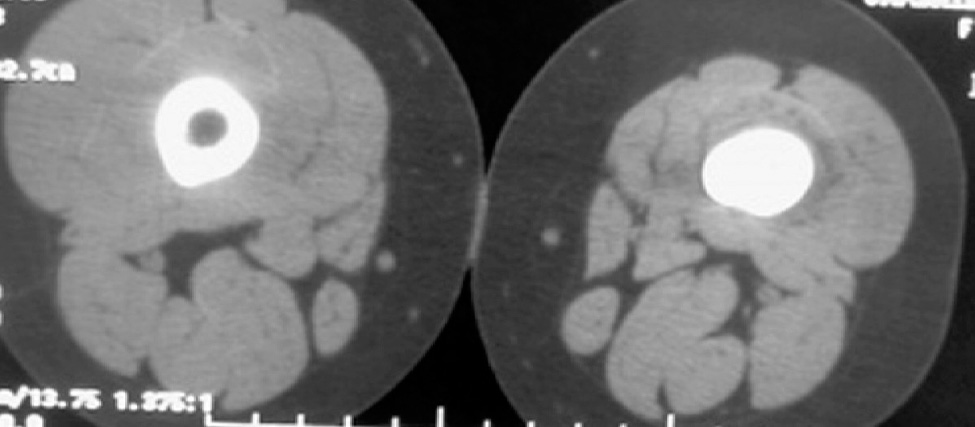

The first conventional radiography of the left thigh revealed soft tissue swelling, sclerosis and mild bone expansion in distal diaphysis of left femur without evidence of cortical destruction and periosteal reaction. CT scan (Figure 1) revealed thick cortical sclerosis with mild edema of bone marrow and MRI comfirmed these findings with mild adjacent soft tissue edema.

Figure 1. CT scan showing a notable sclerosis of distal diaphysis with muscular atrophic changes and mild heterogeneous density.